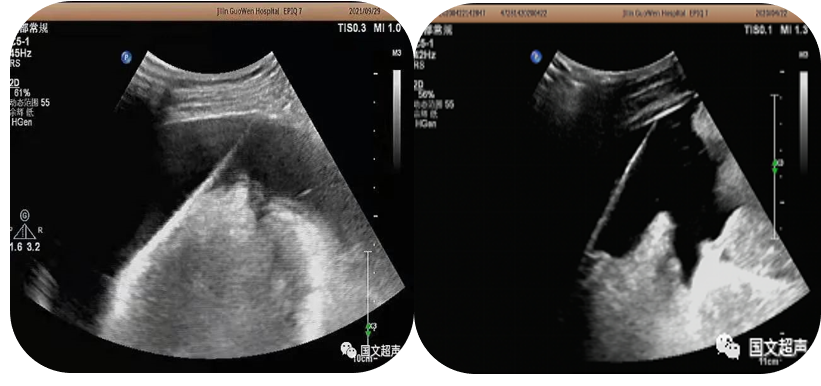

2.超聲引導(dǎo)下置管引流

超聲實時引導(dǎo)下將引流管放置在胸腹腔積液,臟器及間隙膿腫內(nèi)抽取積液減輕癥狀,亦可將藥物注入到某些特定部位從而達到治療效果。

經(jīng)皮肝膿腫穿刺引流

心包積液穿刺引流/腹腔積液穿刺引流